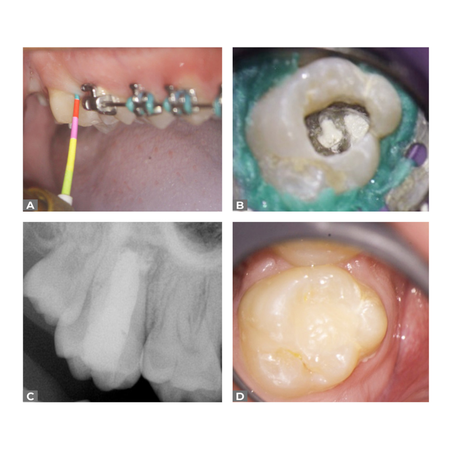

OBJECTIVE: To report the treatment of an endo-periodontal lesion in a maxillary molar with C-shaped anatomy and present complete healing after one year of follow-up with cone-beam computed tomography (CBCT). CASE REPORT: A 15-year-old male patient sought treatment complaining of pain, difficulty chewing, and the presence of a fistula on the buccal mucosa of tooth #17. Fistulography showed the gutta-percha cone extending to the furcation area, while periodontal probing revealed a pocket on...

OBJETIVO: Relatar o tratamento de uma lesão endo-periodontal em um molar superior com anatomia em “C” e apresentar o reparo completo, após um ano de acompanhamento, com tomografia computadorizada de feixe cônico (TCFC). RELATO DE CASO: Paciente do sexo masculino, 15 anos de idade, procurou atendimento relatando dor, dificuldade mastigatória e presença de fístula na mucosa vestibular do dente #17. A fistulografia mostrou o trajeto do cone de guta-percha até a região da furca,...